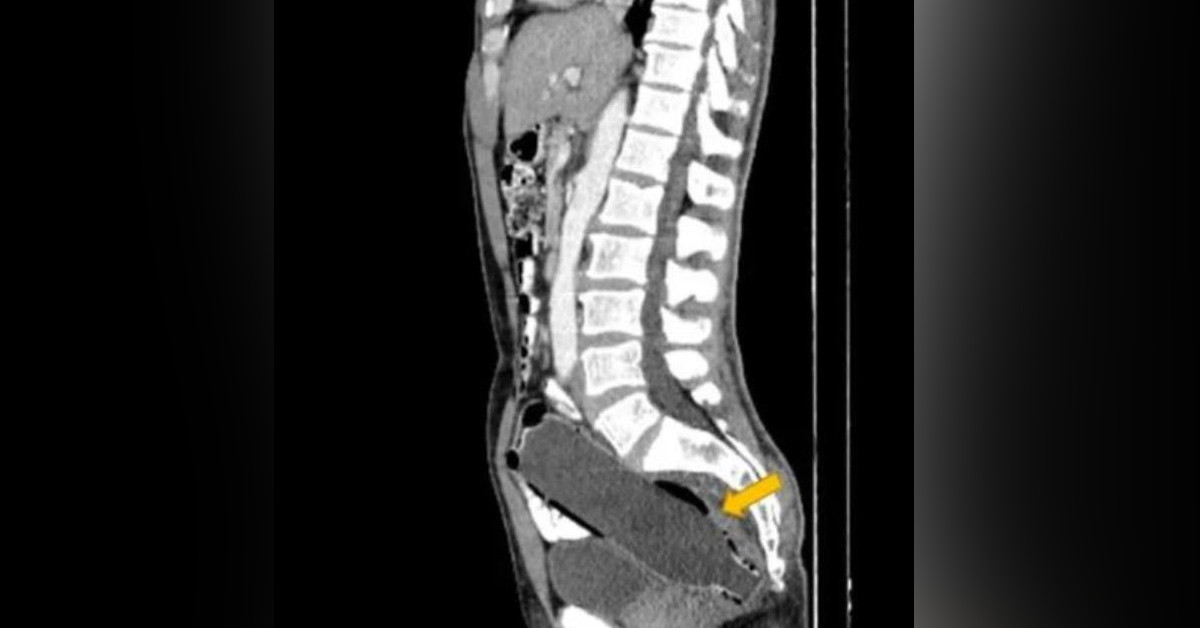

İranlı adamın bütün derdi, çektirdiği röntgen filmlerinin çıkmasıyla doktorlar tarafından anlaşıldı.

Doktorlar detaylı bir incelemenin sonucunda adamın makatında 12 santimetre boyutunda bir pet şişe buldu.